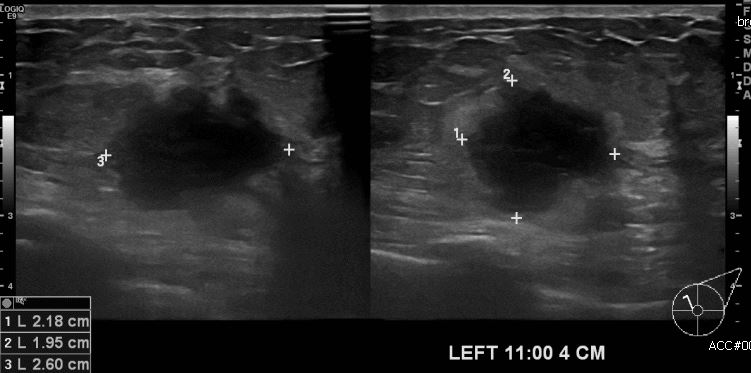

상기환자 좌측 만져지는 멍울과 통증으로 내원하신 60대 여성분으로 본원 초음파상

좌측 11시 방향에서 4cm 떨어진 거리에 의심스러운 멍울 조직검사 시행하여 좌측 침윤성

유관암 진단되었습니다.